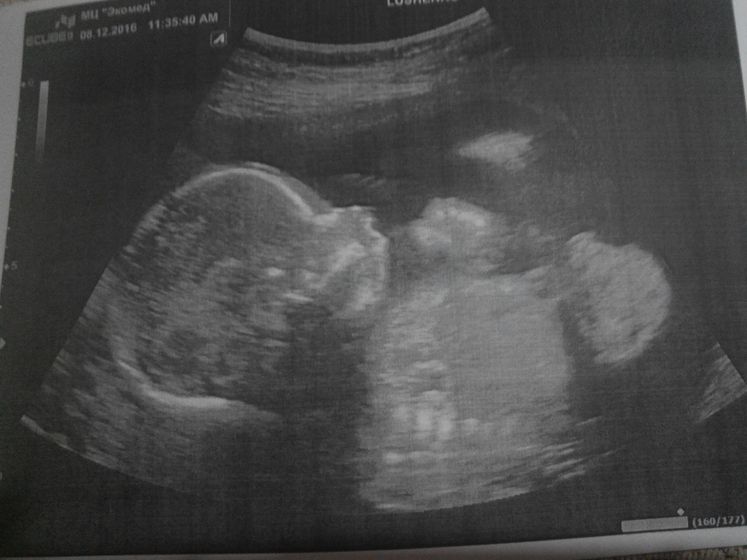

Ой девочки, дождалась я этого дня. Были сегодня с мужем на УЗИ. Узнали пол.

Ждем мы девочку

Очень активная машет ручками и ножками, что то рассказывала пока смотрели её, постоянно открывала и закрывала ротик. ПДР у нас на 25 апреля, как раз мужу на ДР, лучший подарок который только можно сделать))))

Вот такие у нас новости, и покажу вам свою маську.